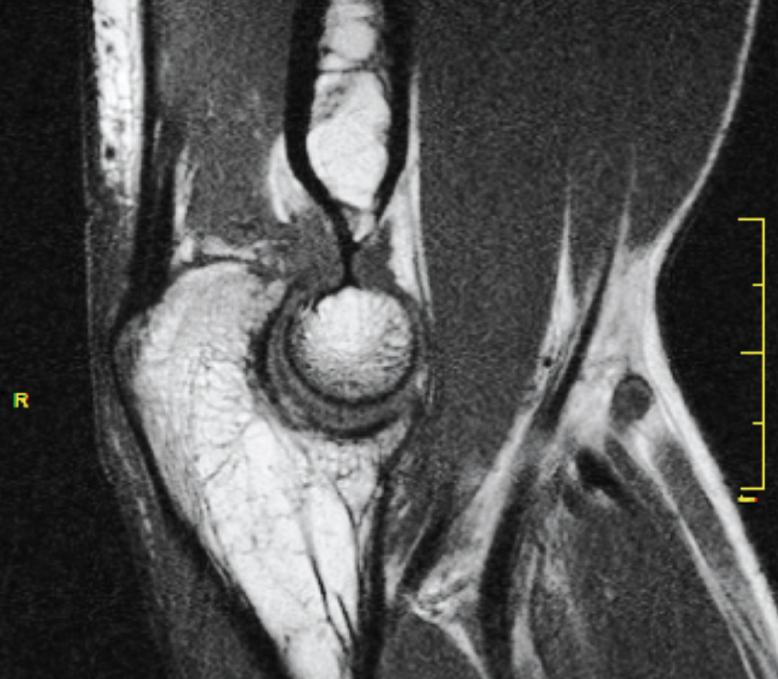

La resonancia magnética (RM) puede ser útil para valorar el cartílago articular, la fibrosis articular y periarticular, el estado ligamentoso y la presencia de cuerpos libres no calcificados (Figura 3).

Figura 3. Fibrosis articular, imagen de resonancia magnética.